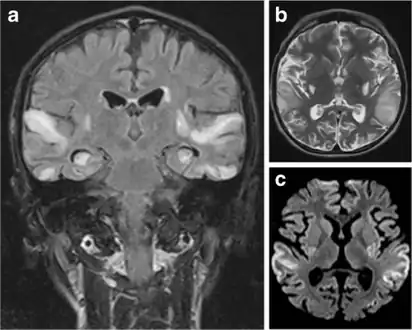

MRI: Multifocal infarct-like cortical areas in different stages of ischemic evolution, areas that do not conform to any known vascular territory. Initial lesions often occur in the occipital or parietal lobes with eventual involvement of the cerebellum, cerebral cortex, basal ganglia, and thalamus.

a)Symmetrical high signal intensities lesions in multiple arterial territories b)high signal cortical and subcortical lesions bilaterally in the edematous superior temporal gyri c)high signal areas in the same regions